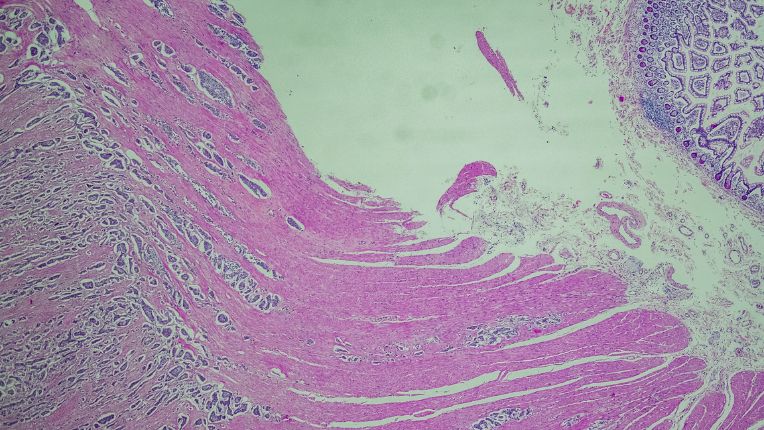

Le diagnostic s'effectue grâce à la biopsie et l'analyse anatomopathologique. On cherchera à classer la tumeur, à distinguer s'il existe une maladie génétique, à mettre en évidence des marqueurs de sécrétion de telle ou telle hormone comme la sérotonine (5-Hydroxy Indol Acetic Acid* (5-HIAA) dans les urines de 24 heures ou dans le sang). Les spécialistes ont recours à l'imagerie médicale afin de repérer la tumeur, réaliser un bilan d'extension et suivre sa progression : échographie, scanner, examens endoscopiques, scintigraphie (TEP-DOTATOC, TEP DOPA ou TEP-FDG). Le choix de l’examen dépend du type de TNE et de son grade.

La chromogranine a est un marqueur recherché au cours du diagnostic de TNE, tout comme la synaptophysine.